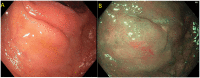

Most colorectal cancers arise from adenomatous polyps and sessile serrated lesions. Screening colonoscopy and therapeutic polypectomy can potentially reduce colorectal cancer burden by early detection and removal of these polyps, thus decreasing colorectal cancer incidence and mortality. Most endoscopists are skilled in detecting and removing the vast majority of polyps endoscopically during a routine colonoscopy. Polyps can be considered "complex" based on size, location, morphology, underlying scar tissue, which are not amenable to removal by conventional endoscopic polypectomy techniques. They are technically more challenging to resect and carry an increased risk of complications. Most of these polyps were used to be managed by surgical intervention in the past. Rapid advancement in endoscopic resection techniques has led to a decreasing role of surgery in managing these complex polyps. These endoscopic resection techniques do require an expert in the field and advanced equipment to perform the procedure. In this review, we discuss various advanced endoscopic techniques for the management of complex polyps.